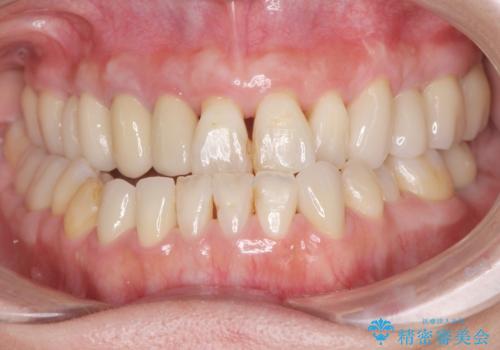

総合歯科治療

インプラント治療&セラミック治療掲載症例数197件

インプラント治療&矯正歯科治療掲載症例数37件

インプラント&根管治療&矯正歯科掲載症例数7件

根管治療&セラミック治療掲載症例数205件

根管治療&矯正歯科治療掲載症例数8件

歯周病治療&インプラント治療掲載症例数74件

歯周病治療&セラミック治療掲載症例数192件

歯周病治療&矯正歯科治療掲載症例数22件